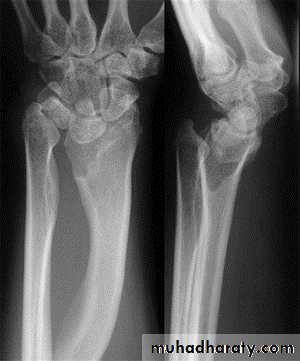

surgeryMadelung deformity

Congenital or posttraumaticLower radius curves forward & medially

Rx : if function affected osteotomyKienbock disease